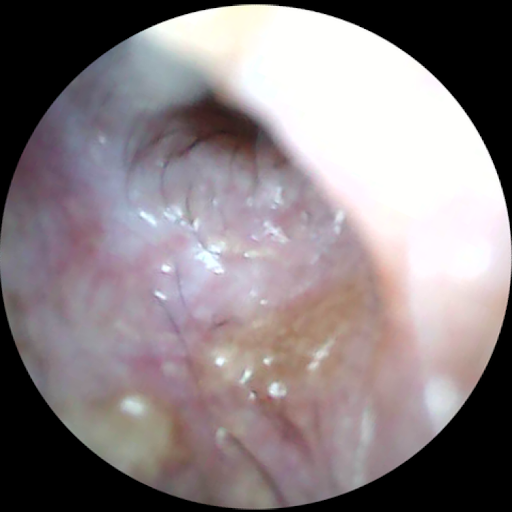

診察の時に、

特に皮膚科の診察では、

耳の中を除くのだが、

ちょっとしたカメラで、

飼い主さんにも一緒に耳の中を確認してもらう。